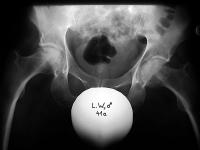

Abbildung 5: Coxa valga subluxans rechts bei spastischer Hemiparese rechts. Der Hüftkopf bereits deformiert, zur Hälfte aus der hochgradig dysplastischen Pfanne luxiert, deutliche Adduktionsfehlstellung durch den Adduktorenspasmus.